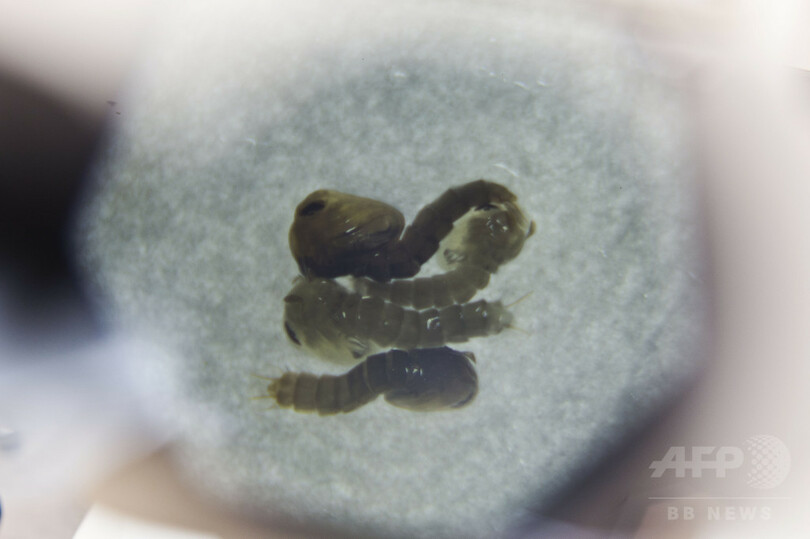

「OX513A」と呼ばれるオスのネッタイシマカには、自然界のメスと交尾して生まれてくる幼虫が、成虫になる前に死ぬよう遺伝子が操作されているため、その繁殖を押さえることができるという。

オキシテックは、十分な数のGM蚊が自然界に放たれれば、広範囲で交尾が行われ、ネッタイシマカの数を大幅に減少、もしくは絶滅に追いやることもできるとしている。